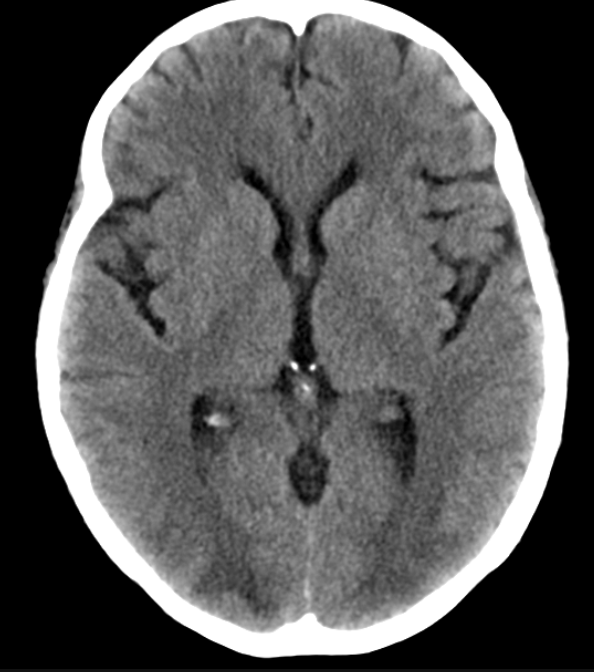

The patient is brought by EMT after being found with confusion, incoordination, and inattentiveness. On review of history, the patient refers to inhaling a substance, but is to droswy to recall the name. On PE he has UMN and ataxia. The following imaging is obtained.

What is Heroin Leukoencephalopathy?